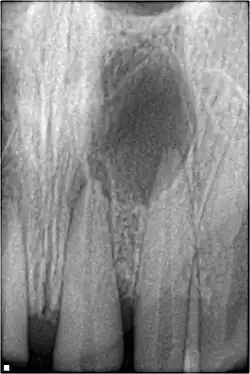

| Fratura de raiz | •Segmento de coroa móvel ou deslocado

•Sensibilidade, devido ao sangramento gengival; •O dente pode estar descolorido (vermelho ou cinza). |

•A linha de fratura envolvendo a raiz será vista, bem como a direção. | Se deslocado:

•Reposicione o dente e verifique a posição com um raio-x; –Contenção flexível usado para estabilizar o dente por pelo menos 4 semanas e, em seguida, reavaliar a estabilidade do dente; •Monitore a cicatrização por pelo menos 1 ano para avaliar o status da polpa. O tratamento do canal radicular será necessário se a necrose pulpar se desenvolver (isso ocorre em ~ 20% das fraturas radiculares²). |

•4 semanas: remoção da tala, exame clínico e radiográfico.

•6–8 semanas: exame clínico e radiográfico. •4 meses: remoção da tala em fraturas do terço cervical, exame clínico e radiográfico. •6 meses: exame clínico e radiográfico. •1 ano: exame clínico e radiográfico. •5 anos: exame clínico e radiográfico. |